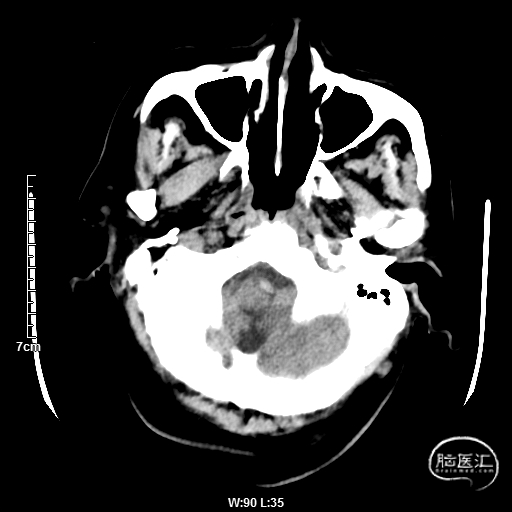

颅脑CT:未见明显缺血/出血病灶。

CTA提示:右侧椎动脉纤细,左侧椎动脉V1、V4段纤细。

MRI提示小脑缺血性改变。

术后CT:未见明显脑出血,双侧小脑低密度影。